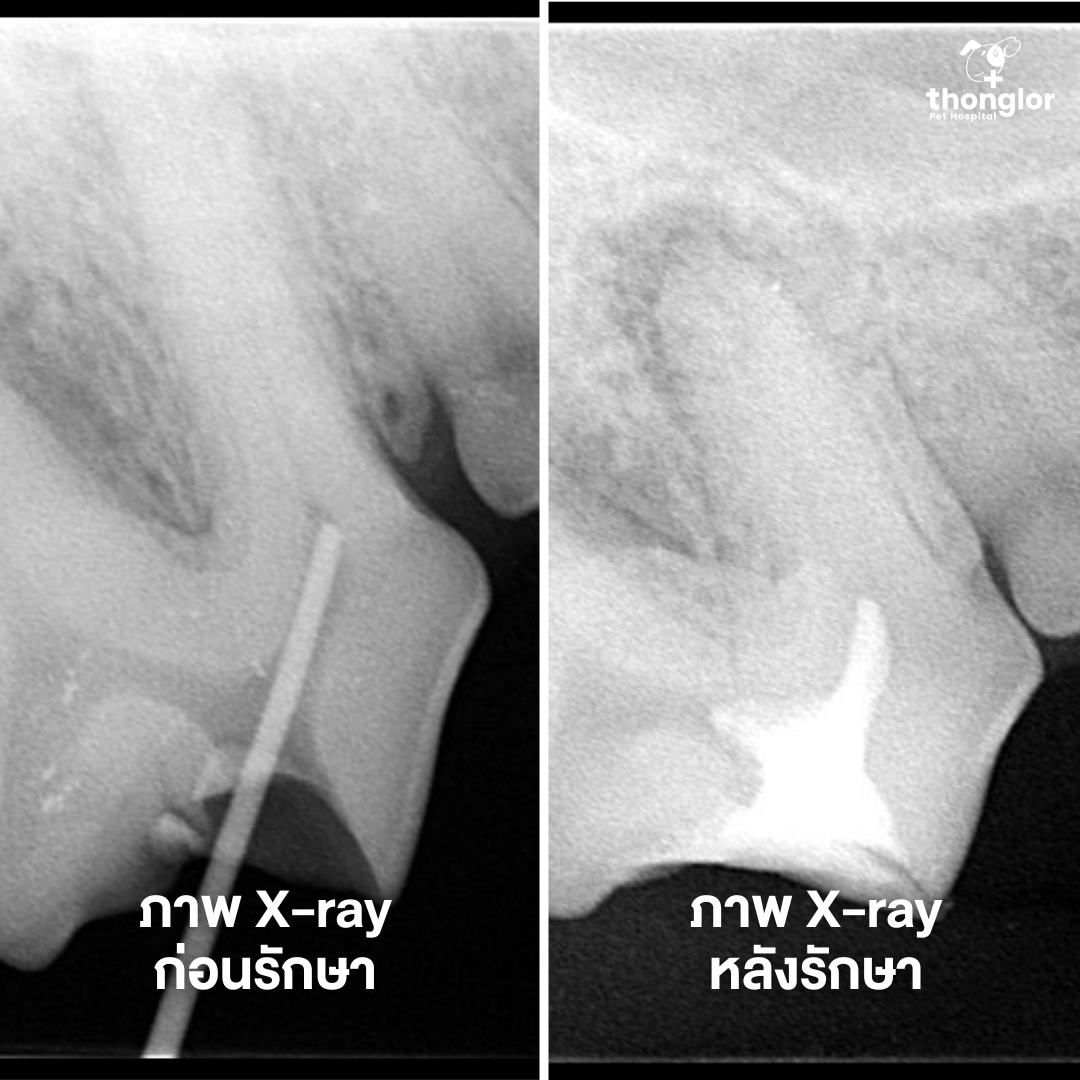

น้องโปเก้ น้ำลายไหลเยอะผิดปกติ ตรวจกับคุณหมอ คลินิกช่องปากและฟันพบว่าน้องเป็น “ฝีที่ฟันกรามซี่ที่ 4 ด้านขวาบน” เอกซเรย์พบรอยโรคทะลุถึงโพรงประสาทฟัน

แต่คุณหมอเลือกรักษารากฟันและอุดฟัน แทนการถอน เพราะฟันซี่นี้เป็นฟันสำคัญที่ช่วยในการบดเคี้ยวอาหาร รักษาไว้ได้จะดีกว่าสำหรับน้องในระยะยาว หลังการอุดฟัน โปเก้กลับมากินอาหารเม็ดได้ปกติ ไม่มีน้ำลายไหล และกลับมาร่าเริงอีกครั้งแล้ว

Poke was experiencing excessive drooling. After an oral examination at our dental clinic, we discovered an "abscess on the upper right 4th premolar." X-rays revealed the infection had penetrated into the root canal.

But our veterinarian chose root canal therapy and dental filling instead of extraction. This is because this tooth plays a crucial role in chewing food. Preserving it provides better long-term benefits for your pet. After the dental filling procedure, Poke was able to eat kibble normally again, the drooling stopped, and he returned to his cheerful self!